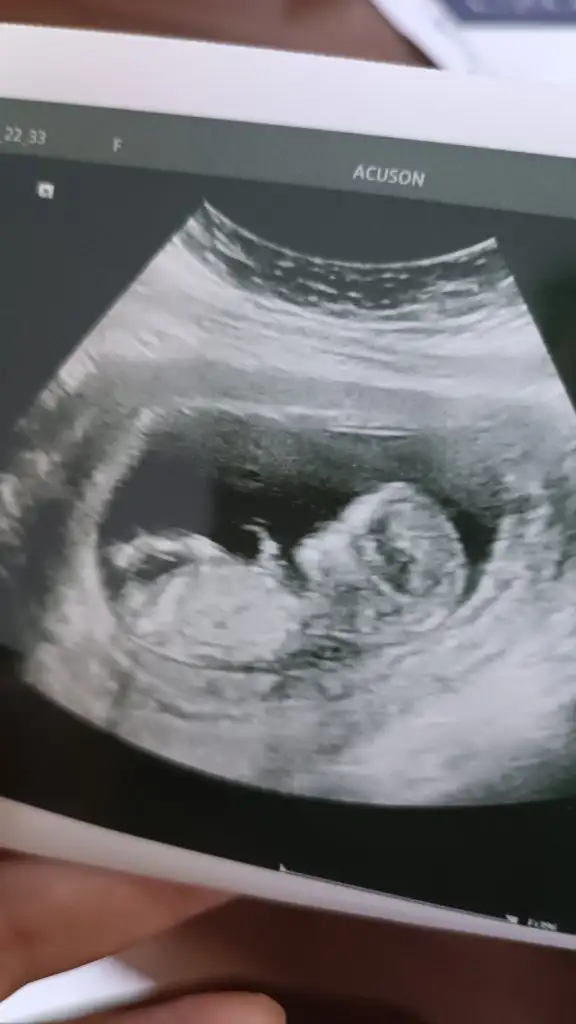

Bana da tahminde bulunur musunuz :)

Erkek bebek buMerhaba bana da tahminde bulunur musunuz

Bana mı dediniz,begenmissiniz ama alintilamamissiniz :)Erkek bebek bu